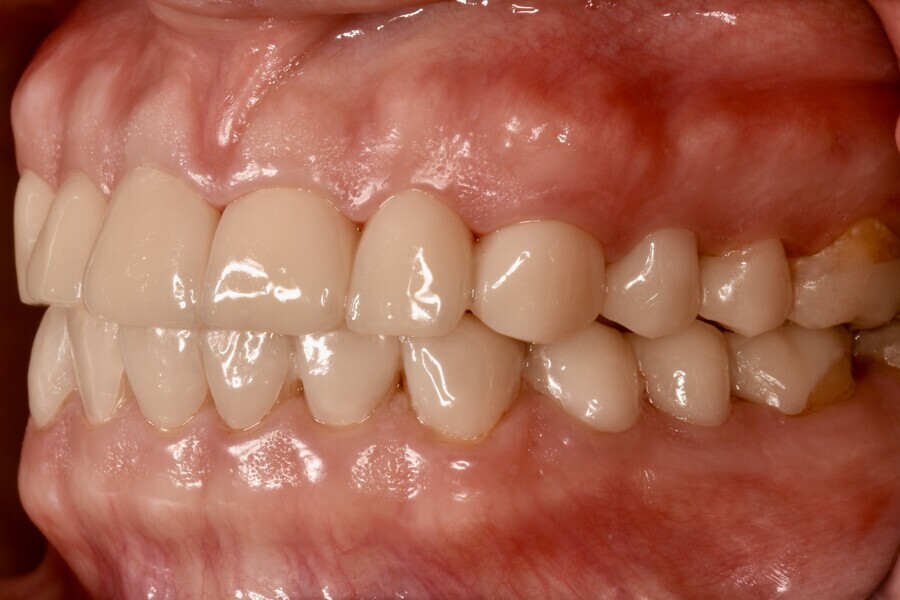

Fig. 1c: Initial situation. Right lateral view.

The clinical and radiographic examination revealed pronounced erosive defects on all teeth (Figs. 1a-f). To prevent nocturnal wear of the remaining tooth structure, an occlusal splint had been prepared by the patient’s general dentist in the past. Quick screening for temporomandibular disorder using the tool developed by the German Society of Craniomandibular Function and Disorders was carried out and revealed no functional abnormalities. The diagnosis was generalised, highly pronounced erosion due to exogenous acid (cola), abrasion and attrition with decreased OVD, multiple carious lesions, dentine hypersensitivity, gingivitis and compromised aesthetics.